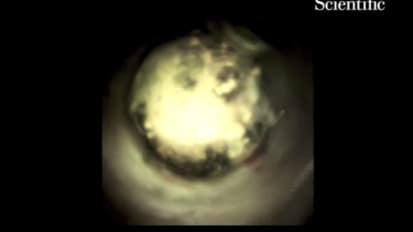

Dr. Raijman performs approximately 1,000 ERCP, 1,000 EUS and 240 cholangiopancreatoscopy procedures per year.